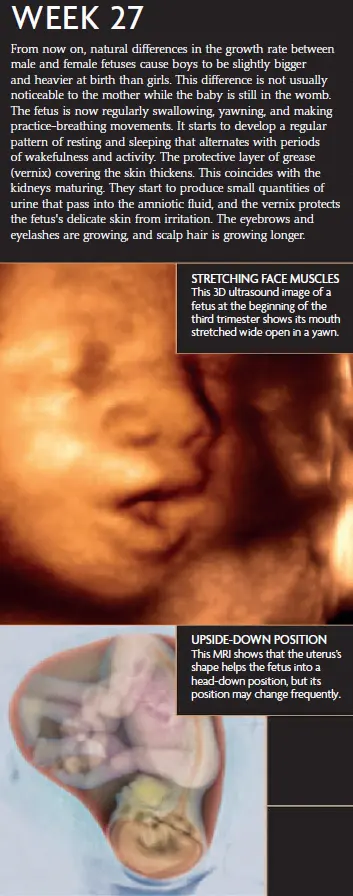

At 27 weeks pregnant, your baby is growing quickly and continuing to develop some crucial systems. Here’s what’s happening:

Your baby’s brain is developing rapidly, and their brain wave patterns are beginning to resemble those of a newborn. It’s amazing to think that their brain is already working hard to prepare for the outside world.

Your baby’s eyes can now open and close, and they can perceive light and darkness. Their hearing is becoming more refined, so they can recognize familiar sounds, including your voice and your partner’s. I remember talking to my baby during this time and imagining how it must feel for them to hear my voice from the inside.

Expect to feel more pronounced movements, such as kicks, turns, and stretches. You might also notice rhythmic, jerky movements — those are likely your baby’s hiccups! At 27 weeks pregnant, your baby’s movements are becoming more coordinated, and it’s exciting to feel them become more active.

Lungs and Breathing

Your baby’s lungs are continuing to develop and produce surfactant, a substance that helps the air sacs inflate after birth. While your baby still has some maturing to do, their lungs are getting stronger every day, and they’re preparing to take their first breaths once they arrive.